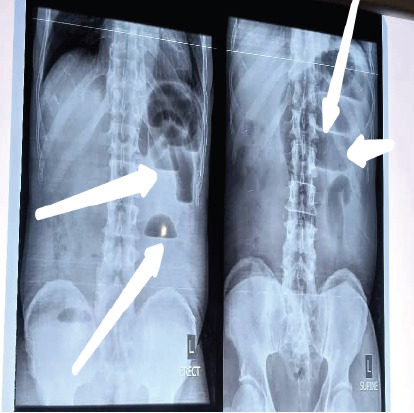

Case: A-72- year old man was seen at the emergency unit of our center with 4 days history of gradual onset of colicky abdominal pain with nausea and vomiting. He had a two-day history of constipation and a one-day history of fever. He was acutely illlooking and his vital signs were abnormal. Urgent abdominopelvic ultrasound and plain abdominal x-ray was performed and were suggestive of intestinal obstruction. He had emergency laparotomy, and intra-operatively appendico-ileal knotting was seen with gangrenous appendix and terminal ileum. This necessitated limited right hemicolectomy and ileo-colonic anastomosis. The patient was managed post-operatively and discharged on post-operative day 10.